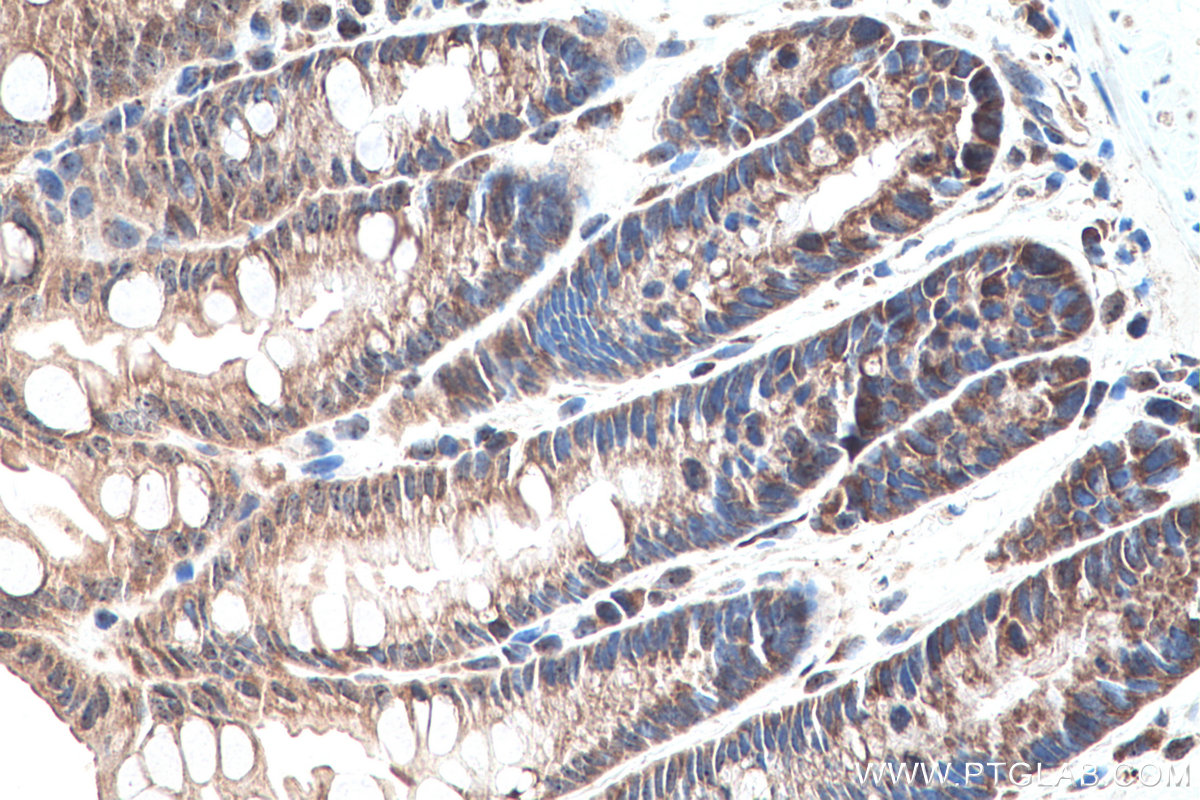

| Positive IHC detected in | mouse testis tissue, mouse colon tissue, rat colon tissue, rat testis tissue Note: suggested antigen retrieval with TE buffer pH 9.0; (*) Alternatively, antigen retrieval may be performed with citrate buffer pH 6.0 |

| Immunohistochemistry (IHC) | IHC : 1:500-1:2000 |